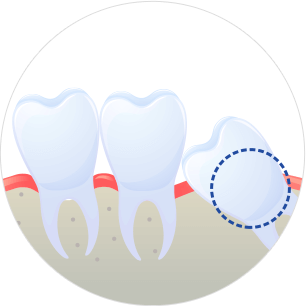

사랑니가 삐뚤거나 누워 난 경우

사랑니가 삐뚤게 자랄경우 주변 치아를 밀어 치열을 불규칙하게 만들거나 뿌리를 압박해 염증과 같은 문제를 유발할 수 있습니다.